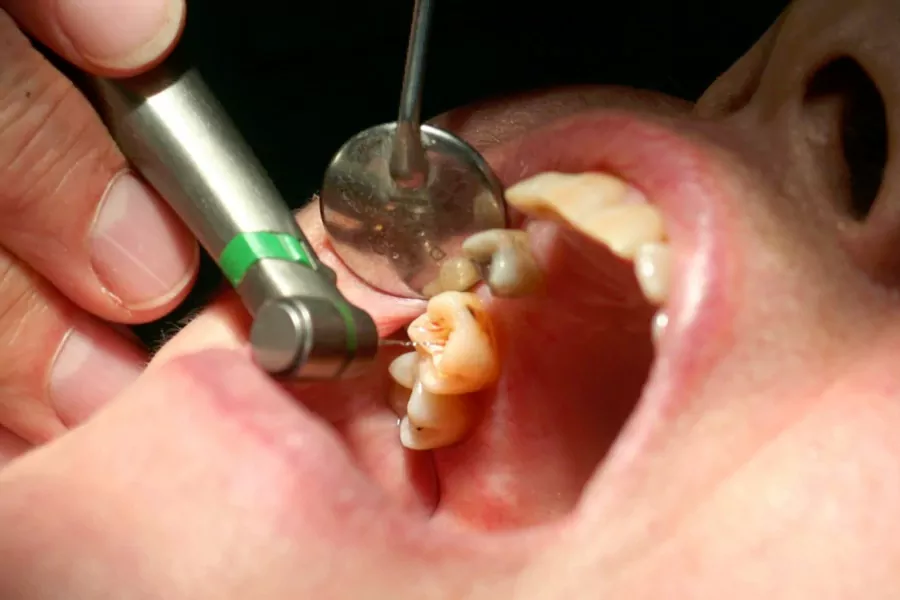

اقدامات انجام شده در طول درمان عصب کشی

پس از معاینات اولیه و بررسی تصویر اشعه ایکس دندان آسیبدیده، در صورت تأیید درمان به روش عصب کشی از سوی متخصص ابتدا محل درمان به صورت موضعی بیحس میشود. سپس در قسمت تاج دندان سوراخی کوچک ایجاد میشود تا دندانپزشک بتواند به حفره و کانال پالپ دسترسی پیدا نماید. بهطور کلی دندانهای ناحیه جلو یک ریشه و یک کانال و دندانهای عقب دهان 2 یا 3 ریشه و 3 یا 4 کانال دارند.

مرحله اول، معاینه و بررسی دندان

در ابتدا دندانپزشک یا متخصص درمان ریشه، دندان آسیبدیده را به صورت کامل معاینه مینماید، سپس وضیعت دندان را با کمک عکس رادیولوژی بررسی میکند تا میزان عفونت و پوسیدگی را تشخیص دهد. به جهت کم شدن درد و ناراحتی بیمار در هنگام درمان، داروی بیحسی موضعی به ناحیه درمان تزریق میکند. دندانپزشک در این مرحله میلهای پلاستیکی به منظور خارج شدن آب و ترشحات، داخل دهان قرار میدهد. سپس متخصص با کمک وسایلی مانند «دریل» و «فویل» پوسیدگیهای روی دندان را برمیدارد و عاج دندان را برای رسیدن به پالپ باز میکند. دندانپزشک با کمک ابزاری کوچک عفونتها را نیز خارج مینماید.